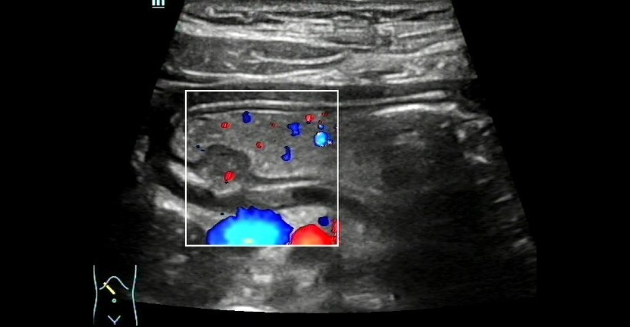

Color Doppler Flow Imaging (CDFI) revealed that a signal indicative of a thin stream of blood flow could be identified near the base of the mass. (Figure 4). Ultrasound indicated a submucosal occupying lesion in the stomach, and ectopic pancreas was suspected.

Ultrasound findings revealed no abnormal changes in the mucosal layer, mucosal muscle layer, muscle layer, or serosal layer on the surface of the mass in this case. The mass was hypoechoic in the wide base of the submucosal layer with a mild central depression at the top, but there was no sound attenuation behind the mass, whose slow movement with the gastric peristaltic wave could be easily confused with the peripheral thick mucosal folds. Therefore, the clinician should wait patiently for the peristaltic wave to subside and the mass contour to stabilize before making a thorough diagnosis of suspicious lesions in the gastric wall. As contrasted with previous studies reporting no blood flow signal in ectopic pancreatic tissue, Color Doppler ultrasound (CDUS) in this case demonstrated a thin stream of blood flow at the base of the mass, thereby expanding our understanding of blood supply to the gastric ectopic pancreas and demonstrating that a blood flow can exist at the base of the ectopic pancreas.